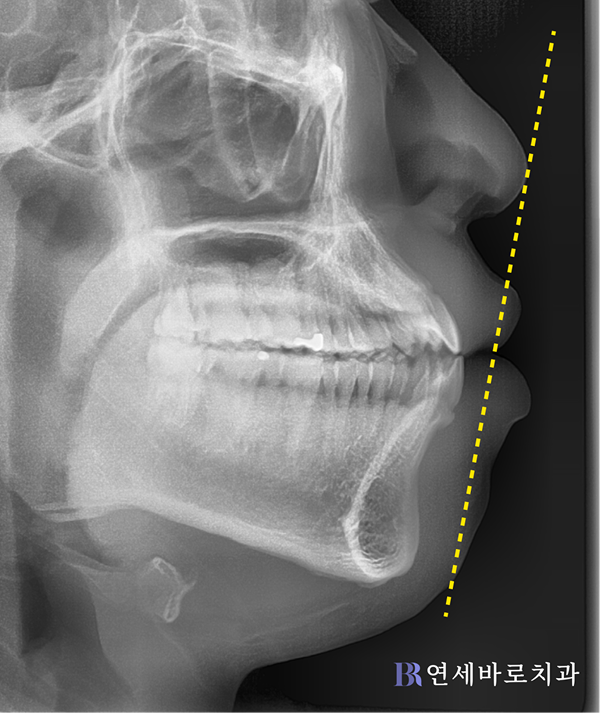

이분의 경우에는 턱뼈 자체가

원인이라고 판단되었습니다.

위턱과 아래턱이 모두 크고,

위치도 앞으로 많이 나왔네요.

그러면서 심미선과 비교하여

입이 많이 나오게 됐습니다.

골격적인 불균형으로 인해

돌출입이 생긴 것으로 보였죠.

돌출입의 원인이 골격 자체의

전후적 부조화에 기인한 만큼,

돌출입 수술을 진행하는 것이

적절하다고 판단되었습니다.